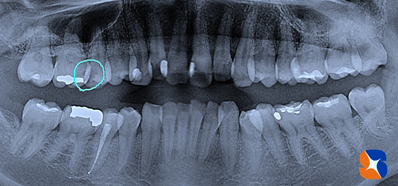

当院では「レントゲンで虫歯=青丸=の説明をされても実際よく分からない」という患者様の声を受けて、治療途中に虫歯の部分をビデオで記録します。その後、テレビモニターで虫歯の画像を患者様に確認してもらってから治療を続けています。